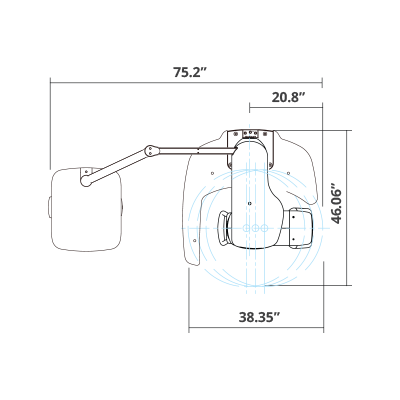

| TYPE | TOP VIEW | FRONT VIEW |

|---|---|---|

|

PaX-i SC (Pano/Scan Ceph) |

|

|